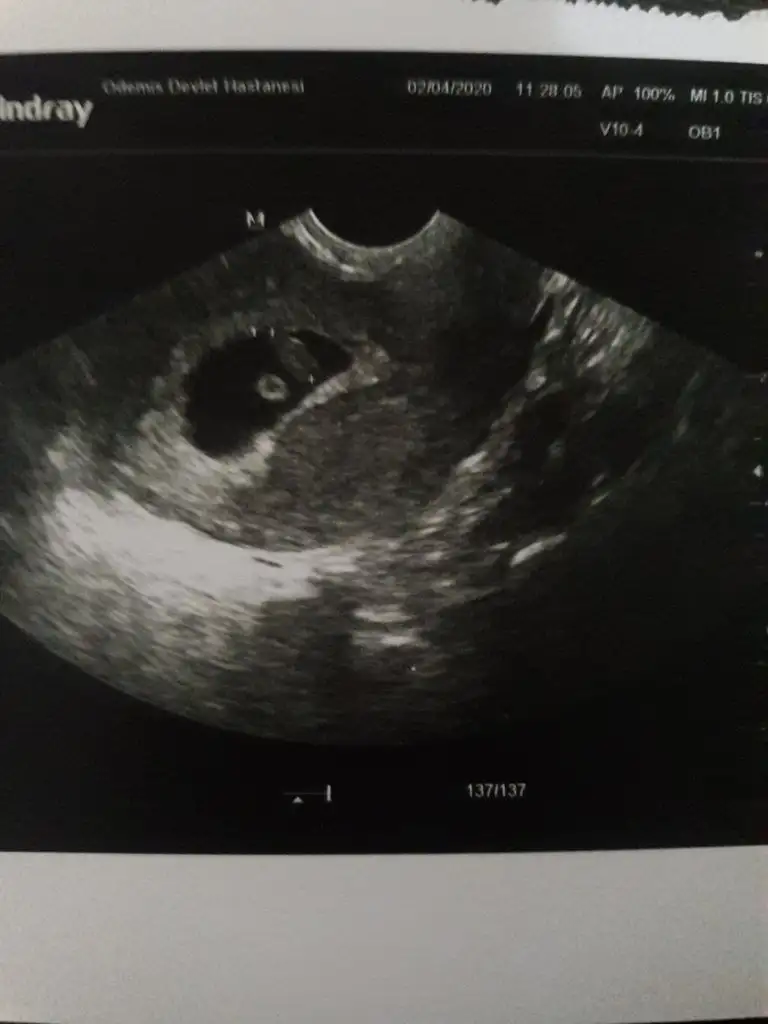

Ben şimdilik tahmininizin kısmen tuttuğunu söylemek için yazdım özellikle.. ultrason fotosunu da ekliyim 12.hafta içinde nub teoremiyle tahminlerinizi alıyım böylece birlikte teyit etmiş olalım şimdiden teşekkür ediyorum :)

Aynen nubu dik erkek 😊 kesinleşince anketimi oylarsanız sevinirim 😊